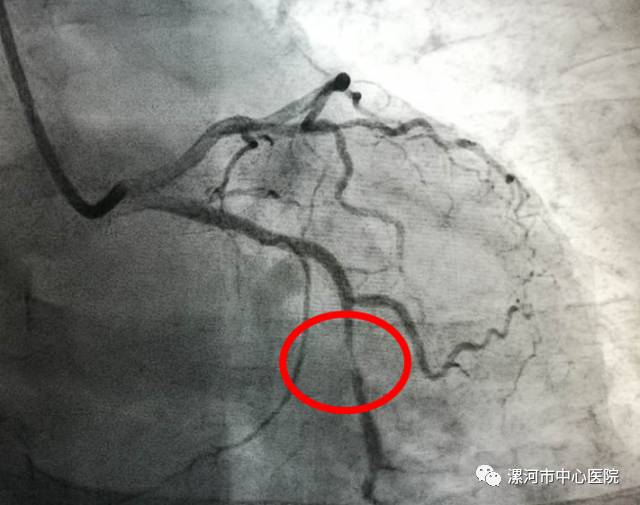

其中一名患者造影显示,术前严重狭窄的血管